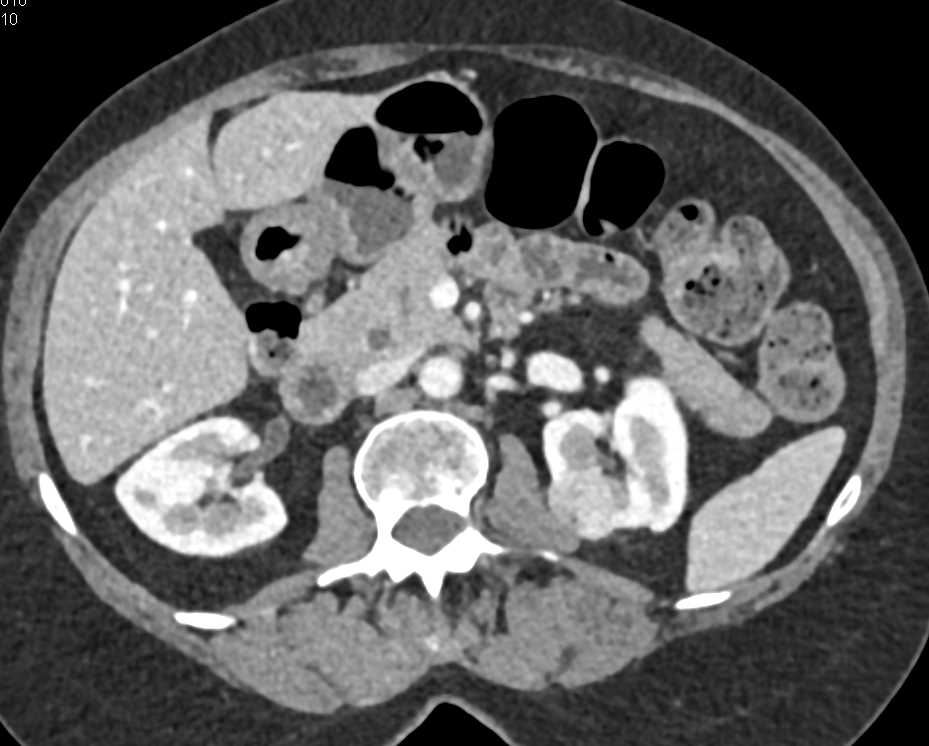

Hepatic Artery Aneurysm